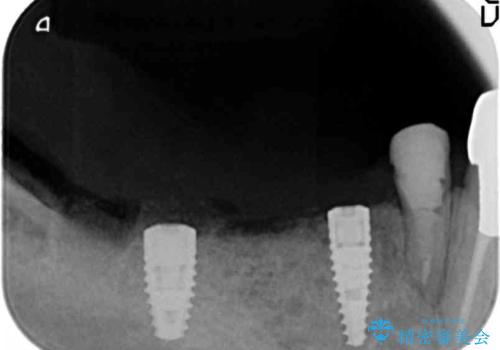

長年の義歯の使用により骨の幅は非常に薄くインプラントを埋入するには大規模な骨の造成が必要な状態です。

インプラントを埋入するには十分な骨の量が必要で、吸収して少なくなってしまった場合でも造成できる場合があります。